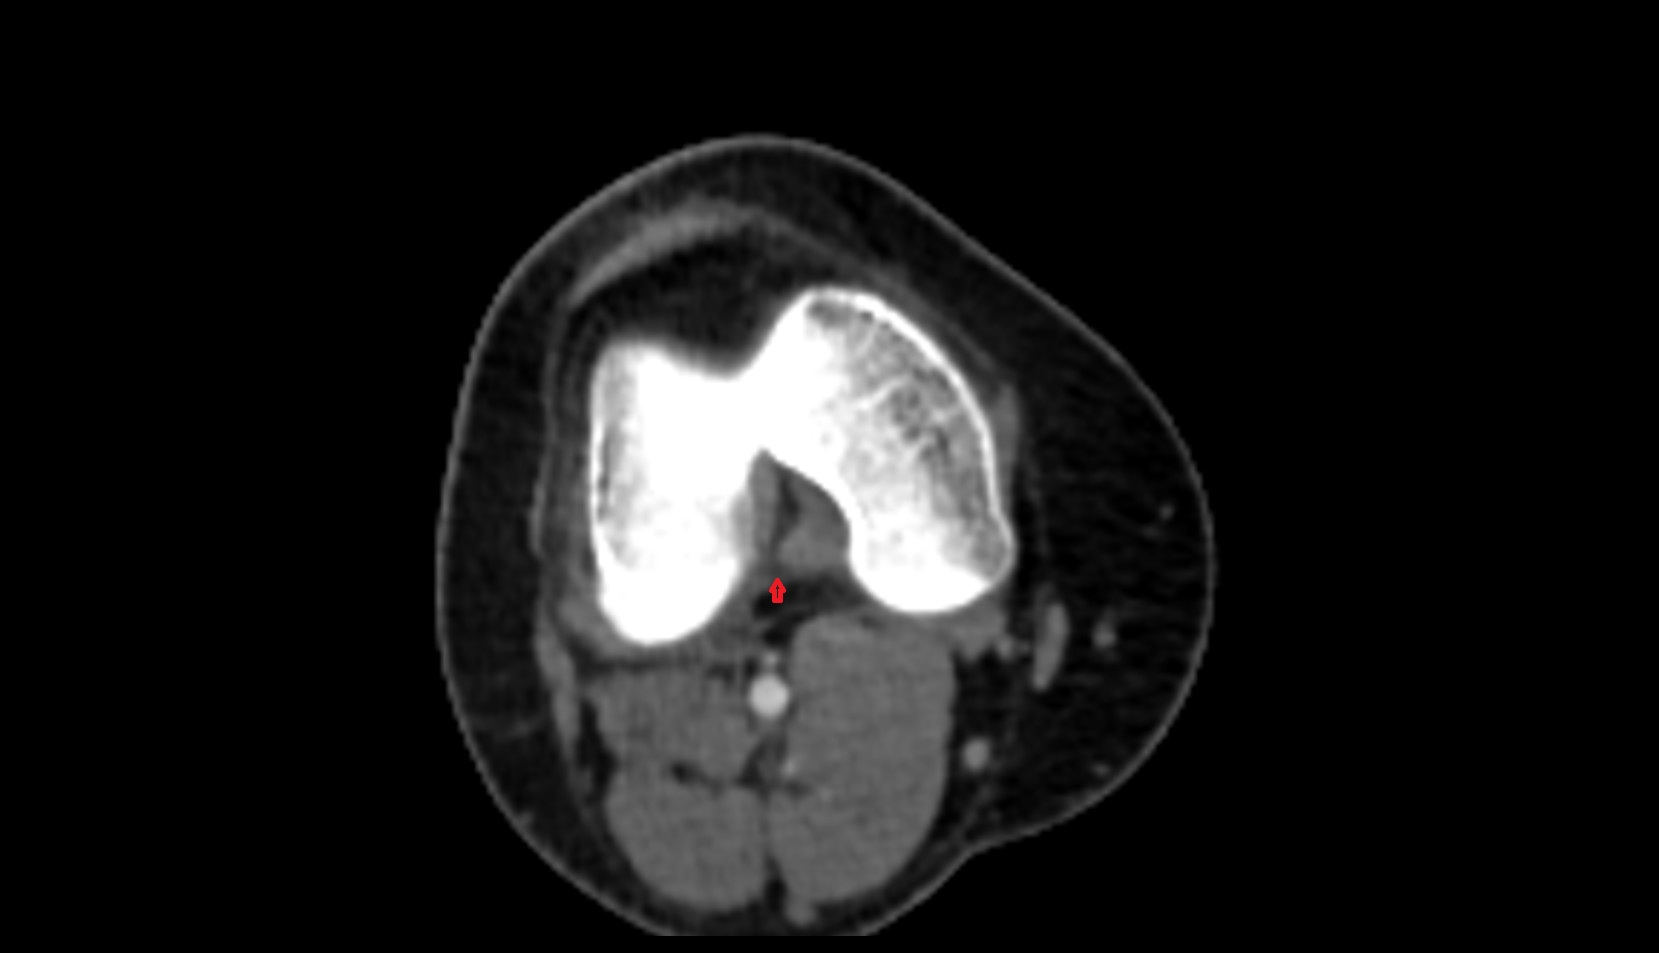

- Anterior cruciate ligament

- Posterior cruciate ligament

- Knee Joint

- Femoral condyle articular cartilage

- Tibial condyle articular cartilage